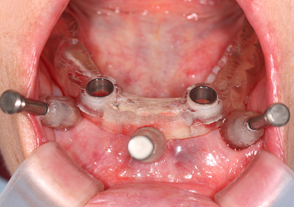

- サージカルガイド

また、オーバーデンチャーに関してのインプラント治療時にも、マウスピース型のサージカルテンプレートを用いてガイデットサージェリー手術を行い、より安全性と正確性を高めたインプラント治療を行っております。